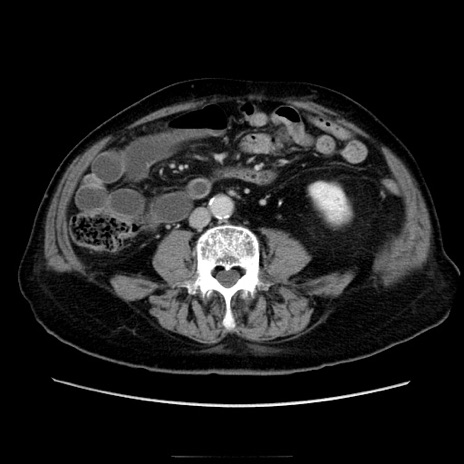

症例21(横断像)

【症例】70歳代男性

【主訴】腹痛

【現病歴】肝硬変・肝細胞癌にてかかりつけの方。約9時間前に食後より腹痛出現。症状が徐々に増悪し、嘔吐出現したため来院。

【既往歴】肝硬変、肝細胞癌(RFA、TACE後)

【身体所見】意識清明、表情苦悶様、BT 36℃、BP 129/78mmHg、P 88bpm、SpO2 97%(RA)、右上腹部から心窩部にかけて圧痛あり、反跳痛なし、筋性防御あり。

【データ】WBC 5800、CRP 0.16